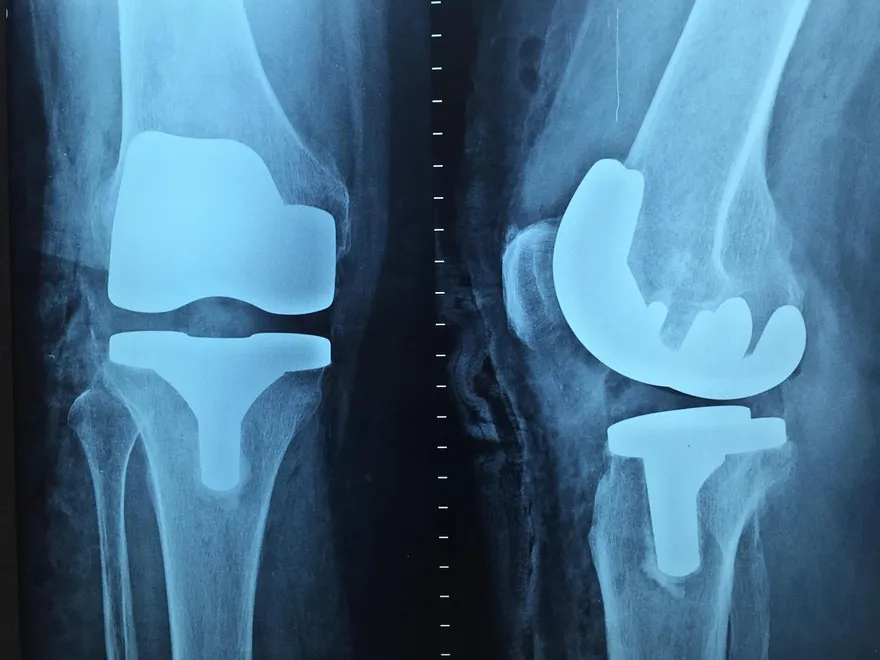

膝蓋磨到骨貼骨!打兩年玻尿酸無效 換人工關節才解決

忍痛15年只吃止痛藥!膝蓋退化到跌倒換雙膝才能走

人工膝關節置換

雙膝置換